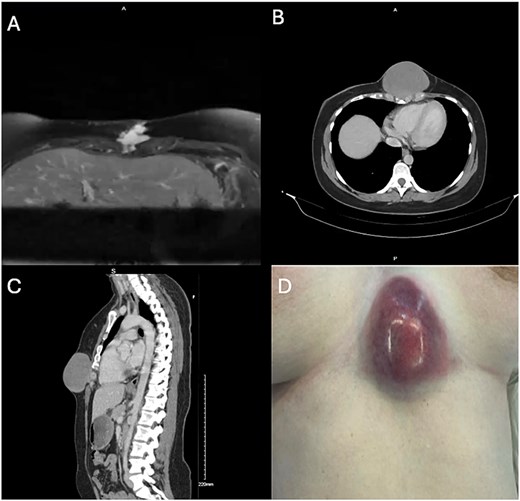

Resection left a 14 × 12 cm defect in the inferior chest wall (Fig. 2D). First, the chest wall was reconstructed using a 20 cm2 acellular porcine dermal collagen-based matrix patch (Permacol® Tissue Science Laboratory, Covington, USA). This was cut to size and secured to the sternum with 2–0 continuous Prolene sutures. (Fig. 3A). A pedicled latissimus dorsi myocutaneous flap was then raised to cover the patch. A prepectoral plane was dissected to create a left submammary tunnel, and the flap transposed anteriorly and positioned free of tension (Fig. 3B). Four Redivac drains were placed before closure of muscles and skin (Fig. 3C).

Post-operatively, the patient’s pain was managed with a thoracic epidural, fentanyl patient-controlled analgesia, and multimodal oral analgesia. There were no postoperative complications, and she was discharged home on postoperative day 12. The wounds have healed well and final histology confirmed the diagnosis of a desmoid tumor with an R0 resection (Fig. 3D).

A: Chest wall reconstruction with Permacol mesh. B: Tunneled pedicled latissimus dorsi flap. C: Closure. D: Wound reviewed at ten days post-operatively.